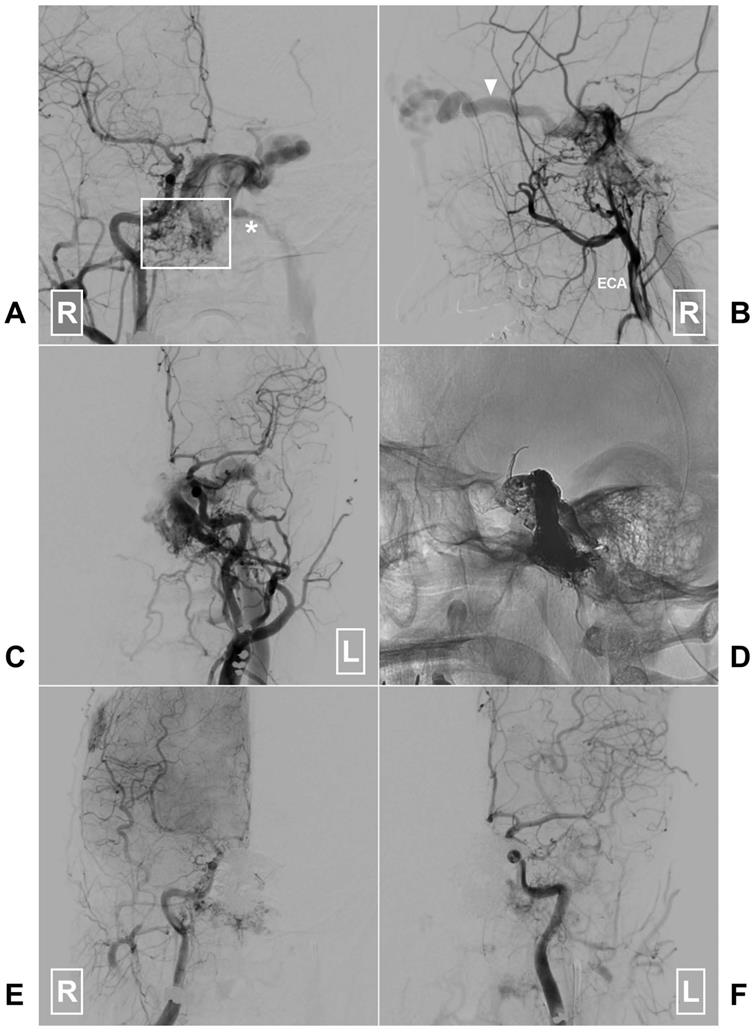

Figure 5

A, Angiogram of the right CCA in AP view reveals a clival DAVF (rectangle) draining to the contralateral IJV (asterisk) via the sigmoid sinus. B, Angiogram of the right ECA in lateral view shows there are multiple tiny feeding arteries. Arrow head denotes the ophthalmic vein drainage. C, Angiogram of the left CCA in AP view shows branches of the left ECA also supply the DAVF. D, X-ray of the cranium shows the Onyx casting after embolization of the through the left IJV. E-F, Angiogram of the right and left CCAs in AP view shows the DAVF is completely obliterated. Abbreviations: AP, anteroposterior; CCA, common carotid artery; DAVF, dural arteriovenous fistula; ECA, external carotid artery; IJV, internal jugular vein; L: left; R, right.